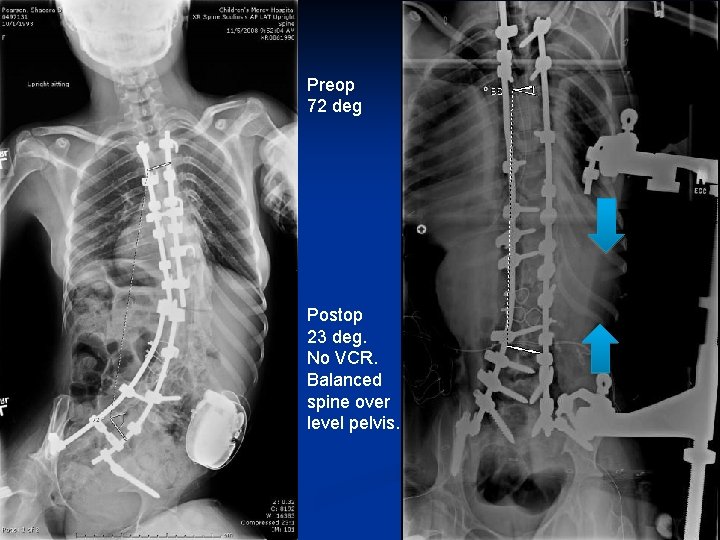

Original surgery Was never Balanced Now pain and broken implants 72 degree scoliosis

Preop 72 deg Postop 23 deg. No VCR. Balanced spine over level pelvis.